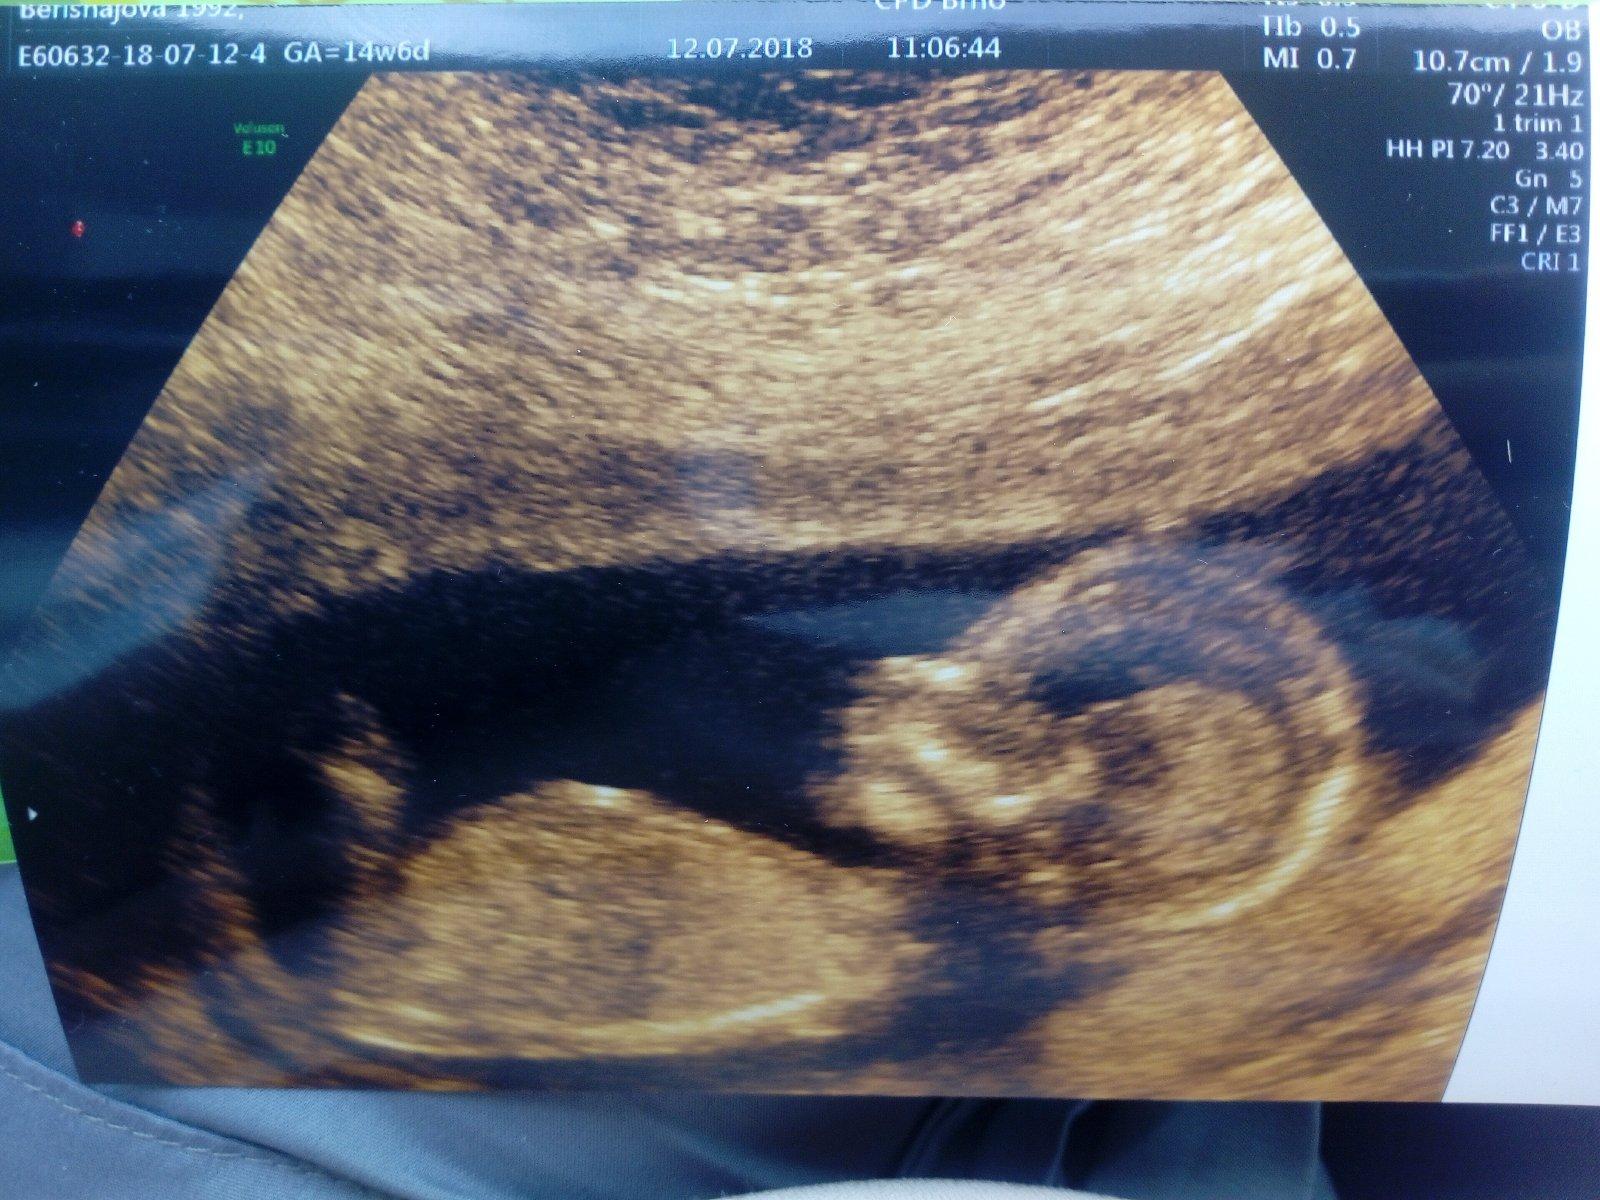

Ahoj holky, tak mame za sebou screening. I.kdyz ne tak úplně. Dle me doktorky je olod mladsi, takže dnes mel byt 13+4tt a mrne krasne idpovida na den.přesně dle MS. Tedy 14+3tt Takze jsme prisli pozdě. Nicméně paní doktorka Bartošovà v prenatalu byla úžasná. Udělala nam uktrazvuk, dle.toho je vse v poradku. Cekaji me tedy triple testy, tak snad to dopadne ok. Jo a pry čekáme druhou holčičku, ale ja mam pořád pocit, že to bude chlapeček. Nevím proc. Každopádně tak jako tak hlavně že bude mrne zdravé. =)

@priefi No noje gyndsrka porad tvrdila, ze je plod o tyden mladsi, pak zase o dva dny uz jen... mne se to ale nezdalo, protoze vím přesně, kdy jsem mela ovulaci. Rekla, ze se mam objednat s tim týdnem, co mi ona vypočítala a že vyšetření mam absolvovat nejpozději do 5.7. Tak sem tam zavolala a sestra, ze me objedna na 12.7. Tak jsem ji rikala, ze to uz je ale pozdě, ze moje mudra rikala, ze do 5.7. to mam.mit. No a sestra, ze oni to počítají jinak a ze podle toho, co jsem.ji zadala bych mela byt 13+4tt coz je úplně v pohodě. No samozřejmě uz jak mi brala sestra krev, tak rikala, ze si mysli, ze plod bude normalne odpovídat podle MS a aby nebylo pozde na screening. To sama doktorka, ještě než zapla.utz. A taky že jo. Plod odpovídá presne dle MS. Takze říkala, ze i kdyby se snazila z toho udelat 13+6tt tak plod je o dost vetsi a ty hodnoty uz vy byly prostě zkreslený. Tak mi udelala ason ultrazvuk a dle toho je miminko zatim uplne v pořádku. Projasneni, srdicko, mozek, organy, nisni kustka... vse ok. Tak snad... Akorat bohužel budu absolvovat ty tripple testy no =( to.me štve. Dnes k ni jdu, tak jsem zvedava, co.mi na to řekne. Jsem nasrvana i na ni, protože ma strašně zastaraly utz a tolikrat me měřila a porad byla přesvědčena, ze plod je určitě menší.